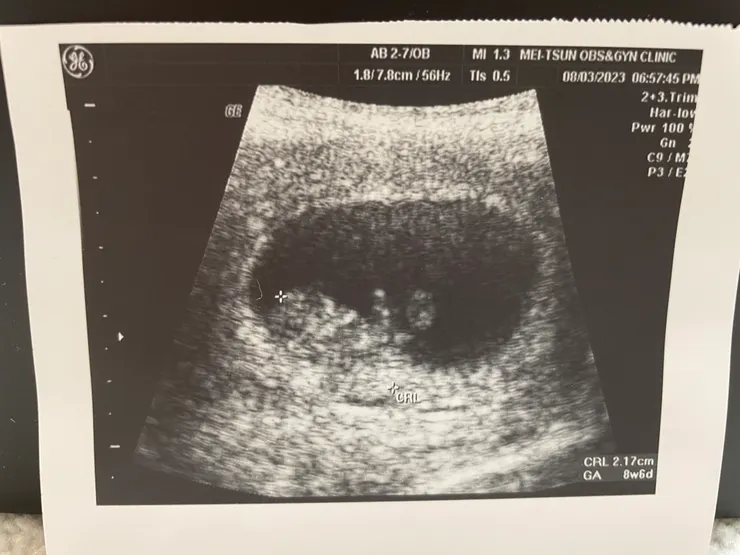

8W+6的小福氣~ 2.17cm

由於第一間診所有抽血檢驗,所以過了一週要去看報告,小福氣可可愛愛的招手~心想我們又平安度過這一週了~ 殊不知血液報告出來,第一週打的針效果不大D-DIMER只降到0.95,醫生說要換針~一天打兩針而且比較痛...我的老天鵝阿內心狂吶喊~醫生還問我怎麼樣? 我說能怎麼樣就只能這樣啊!!不然怎麼辦 ToT